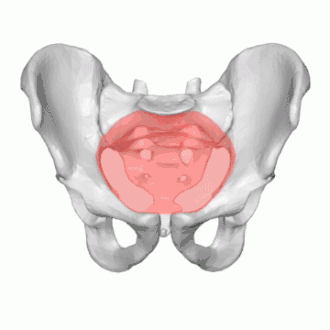

Pelvic inlet

The pelvic inlet or superior aperture of the pelvis is a planar surface which defines the boundary between the pelvic cavity and the abdominal cavity (or, according to some authors, between two parts of the pelvic cavity, called lesser pelvis and greater pelvis). It is a major target of measurements of pelvimetry.

Its position and orientation relative to the skeleton of the pelvis is anatomically defined by its edge, the pelvic brim. The pelvic brim is an approximately apple-shaped line passing through the prominence of the sacrum, the arcuate and pectineal lines, and the upper margin of the pubic symphysis.